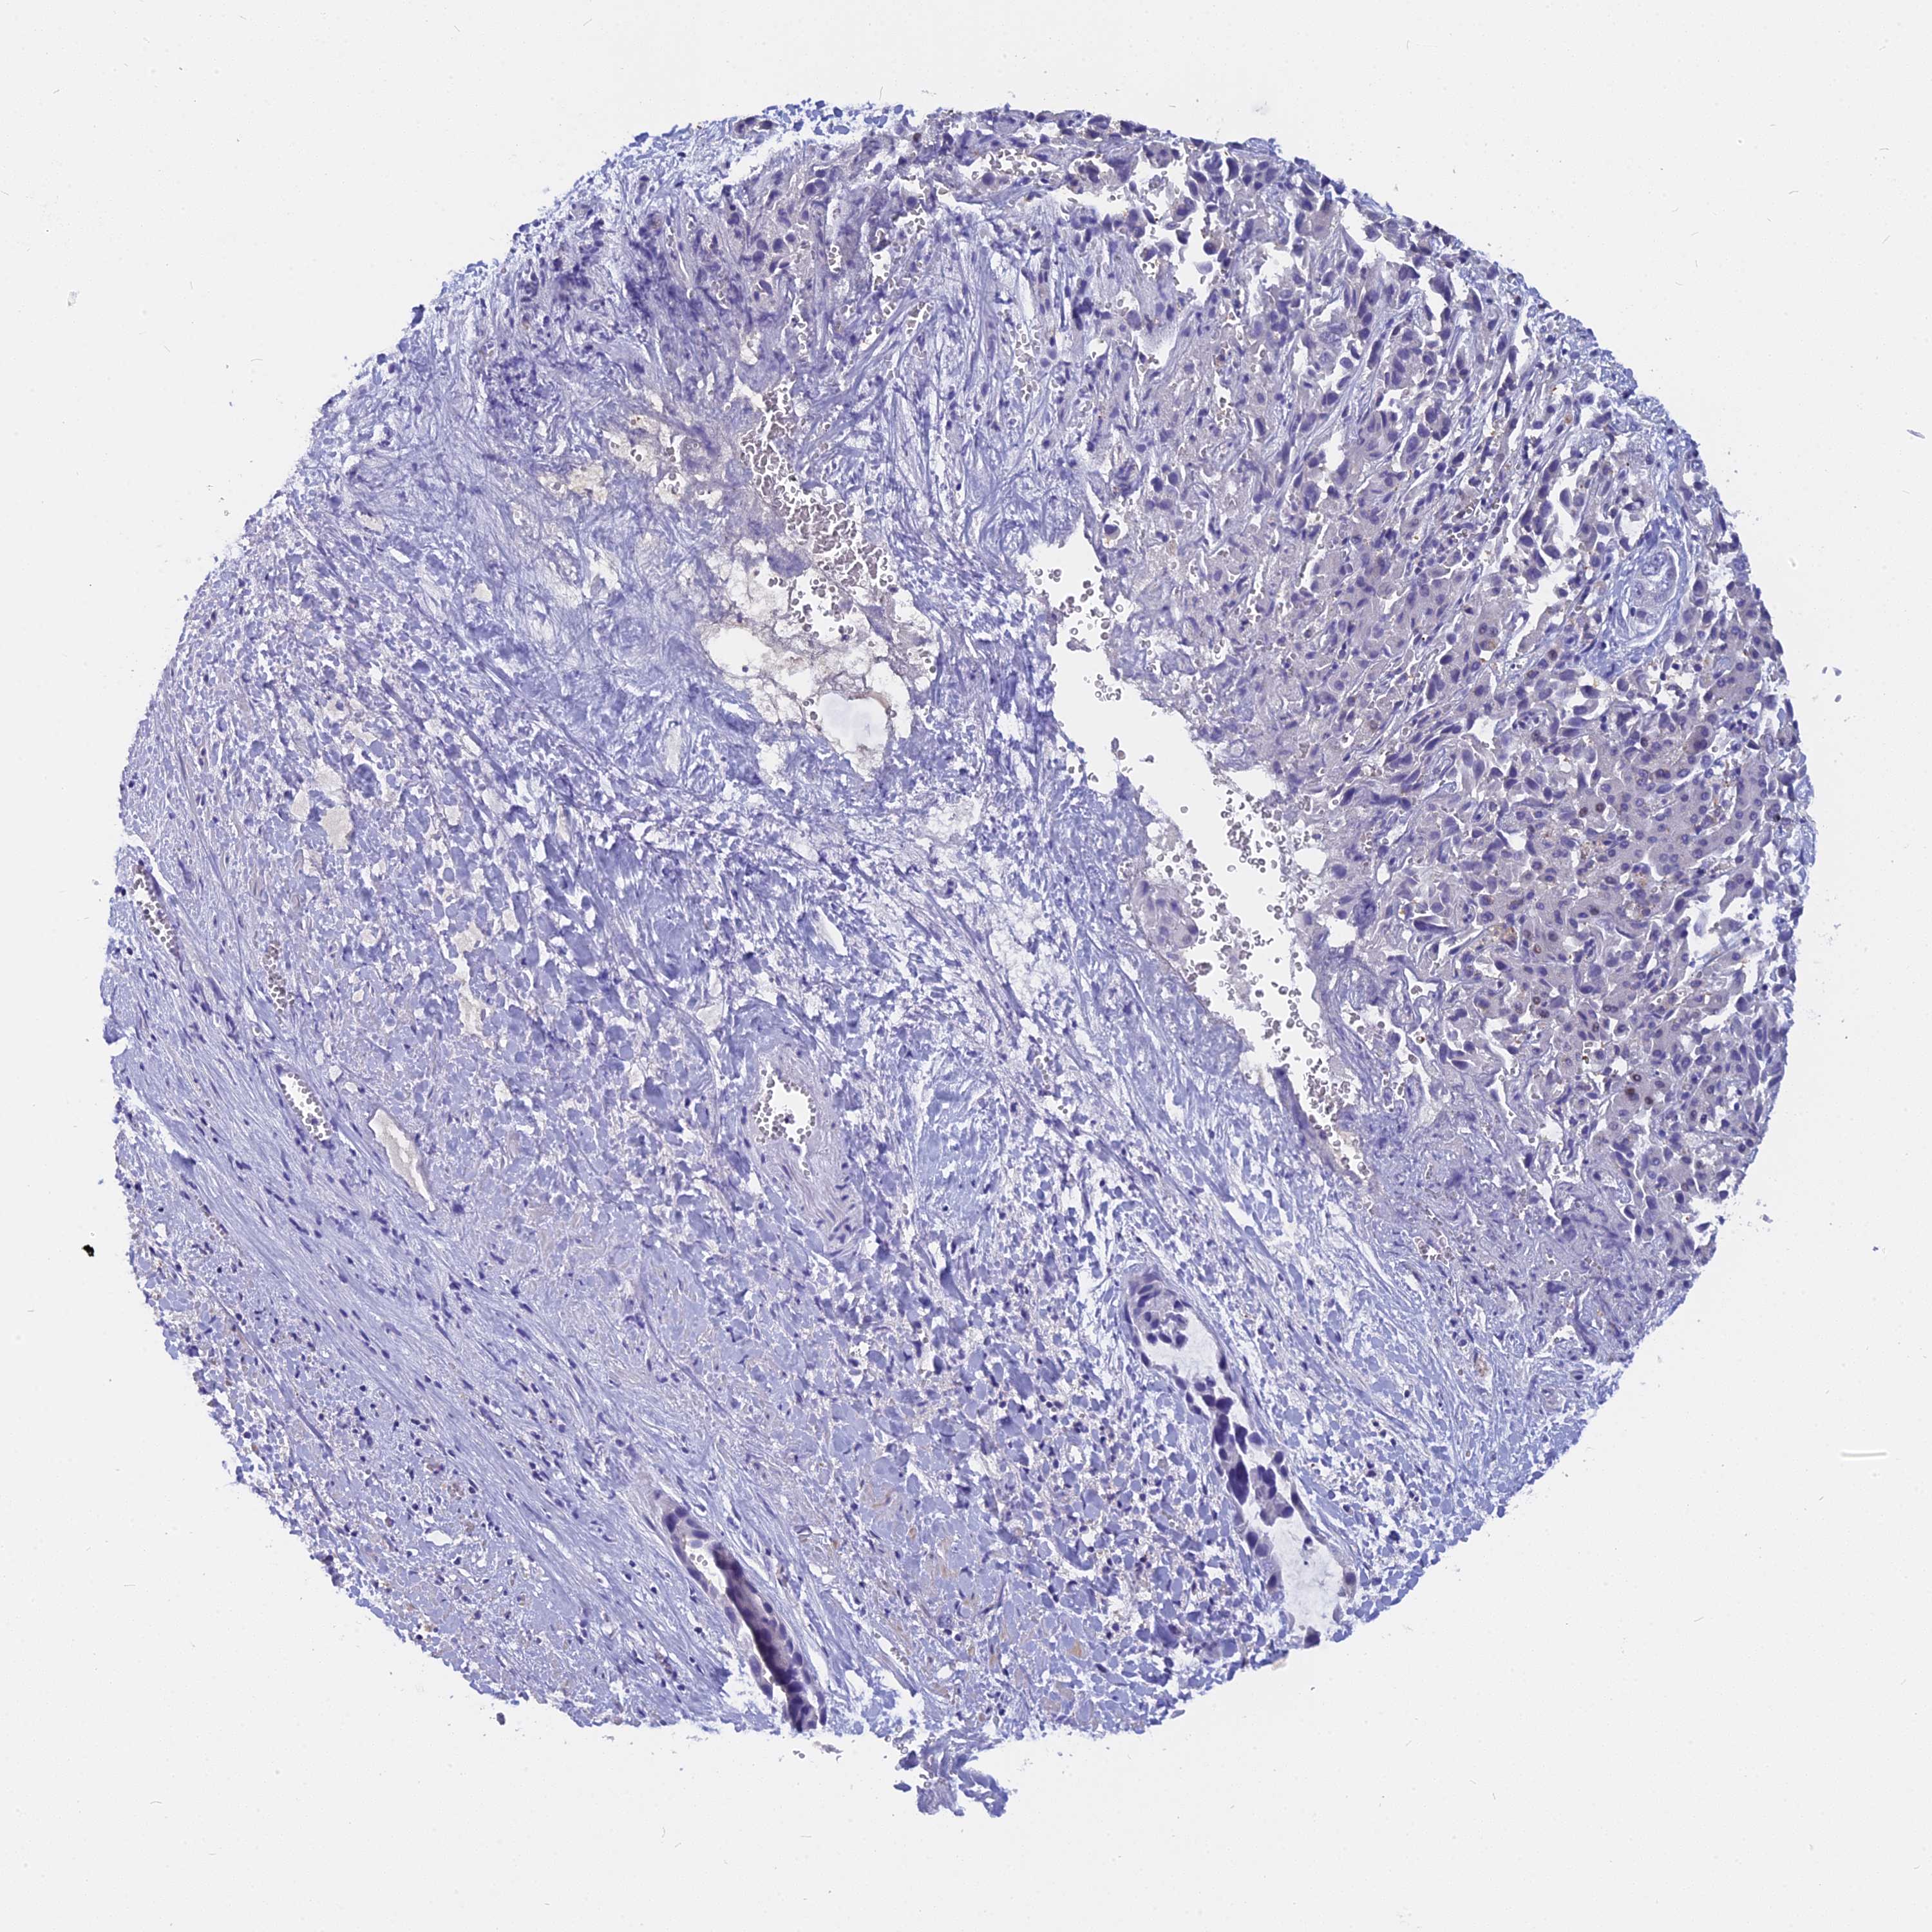

LIVER CANCER - Protein expressioni

A mouse-over function shows sample information and annotation data. Click on an image to view it in a full screen mode. Samples can be filtered based on level of antibody staining by selecting one or several of the following categories: high, medium, low and not detected. The assay and annotation is described here.

Note that samples used for immunohistochemistry by the Human Protein Atlas do not correspond to samples in the TCGA dataset.

Antibody stainingi

Antibody staining in the annotated cell types in the current human tissue is reported as not detected, low, medium, or high, based on conventional immunohistochemistry profiling in selected tissues. This score is based on the combination of the staining intensity and fraction of stained cells.

Each image is clickable and will lead to virtual microscopy that enables deeper exploration of all samples and also displays staining intensity scores, fraction scores and subcellular localization as well as patient and tissue information for each sample.

Antibody HPA043339

Staining

High

Medium

Low

Not detected

Intensity

Strong

Moderate

Weak

Negative

Quantity

>75%

75%-25%

<25%

None

Location

Nuclear

Cytoplasmic/membranous

Cytoplasmic/membranous,nuclear

Cholangiocarcinoma

Carcinoma, Hepatocellular, NOS